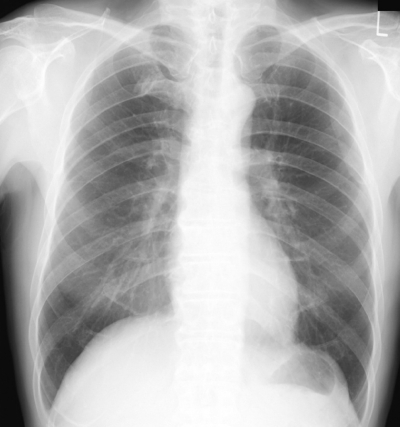

検査所見:尿所見:蛋白(-)、糖(-)。血液所見:赤血球 450 万、Hb 13.3 g/dL、Ht 40 %、白血球 6,200(桿状核好中球 2 %、分葉核好中球 58 %、好酸球 3 %、好塩基球 1 %、単球 8 %、リンパ球 28 %)、血小板 18 万、D ダイマー 0.6 μg/mL (基準 1.0 以下)。血液生化学所見:AST 32 U/L、ALT 45 U/L、LD 260 U/L(基準 176〜353)、CK 98 U/L(基準 30〜140)、尿素窒素 11 mg/dL、クレアチニン 0.9 mg/dL。心筋トロポニン T 陰性。胸部エックス線写真と心電図とを別に示す。心エコーで前壁から心尖部にかけて軽度の収縮性低下を認める。